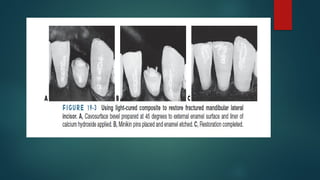

 large Class IV preparation on the distal surface of a canine

that involves a significant amount of the distoincisal corner.

 Rarely used in anterior teeth or with composite restorative

materials.